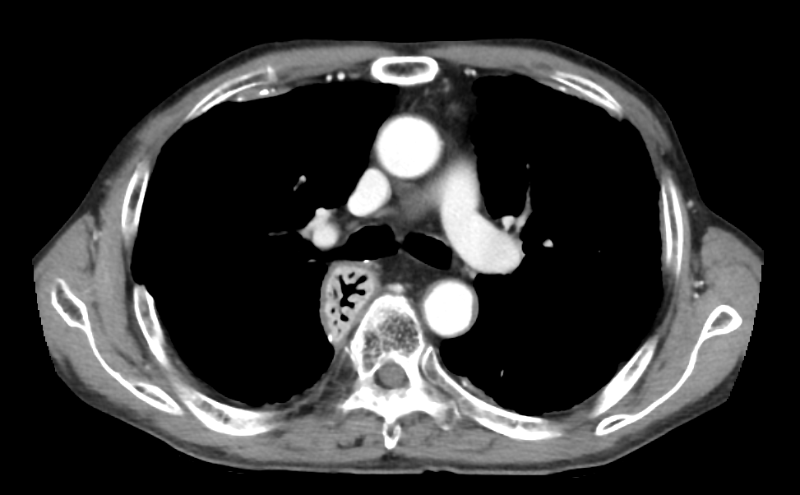

700床を超す著明な国立A病院で肺がんの治療を十分に受けていた建設大工さんの胸部CT写真が写真1です。明らかな胸膜プラークを認めるのですが、その病院の呼吸器内科医も放射線科医も全く認識していませんでした。そんな中、ご家族がアスベスト(石綿)による可能性を疑い、病院の事務でCD-ROMを借用し、セカンド・オピニオンとして、アスベスト関連疾患の専門医がいる「ひらの亀戸ひまわり診療所」に読影依頼をしました。

写真1 国立A病院 胸膜プラーク